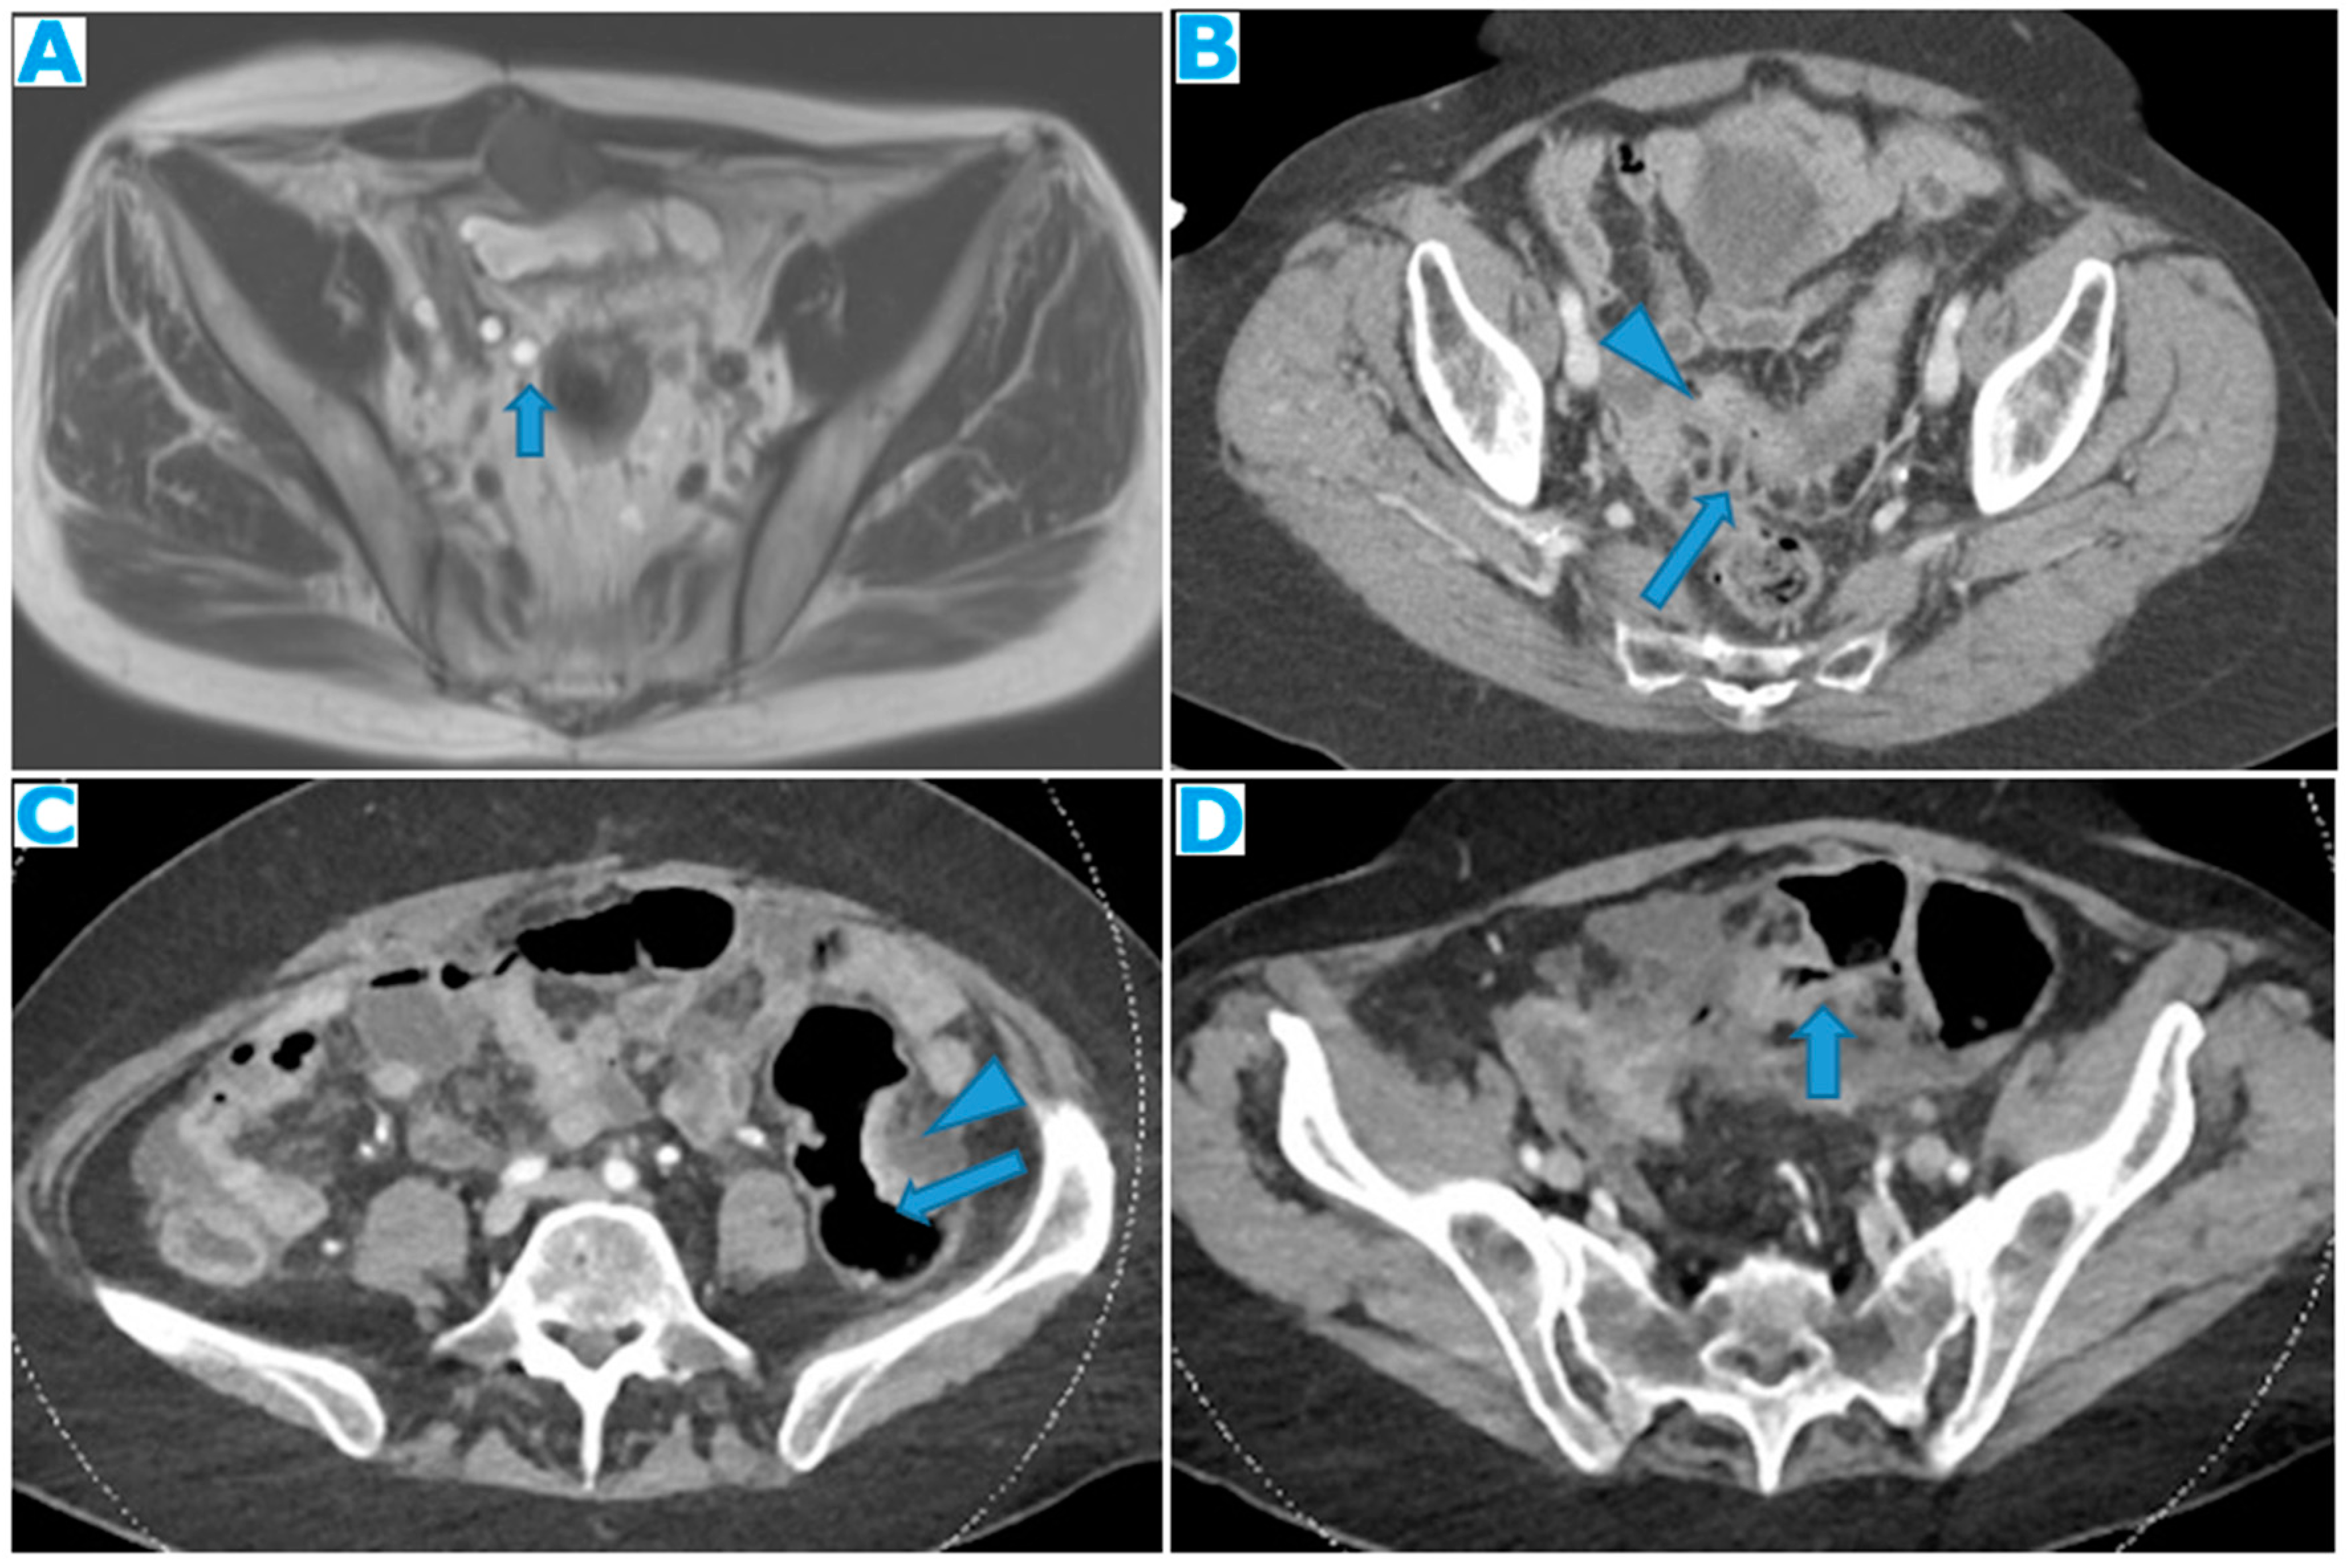

Figure 33.

Axial CE portal phase FST1WI (A). PC from duodenal adenocarcinoma: Deposit seeding within the peritoneum that covers the left pelvic wall, which looks diffusely thickened (arrow). Axial CE-CT (B). PC from undifferentiated caecal adenocarcinoma: Nodular deposit within the peritoneum that covers the left pelvic wall (arrow).

Figure 35.

Axial CE-CT (A, B, C). Axial T2WI (D and E), DWI (F). PC from mucinous adenocarcinoma of the appendix: Notice the peritoneal deposit within the left lateral pelvis (arrow on A) as an elongated soft tissue mass. The patient presented with a left uretero-hydronephrosis (* on B) due to the pelvic deposit which obstructed the ureter (arrowhead on C). Paravesical spaces are peritoneal recesses that cover on each side the distal ureter, the seminal vesicle, and the deferent duct. Note the deposit within the left paravesical space and how it obstructs the left ureter (arrow on C). The deposit also follows the course of the left deferent duct (arrow on E and F).